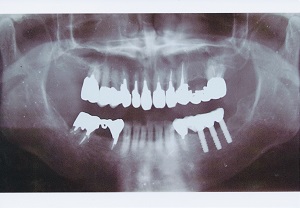

インプラント症例

■その1

before

after